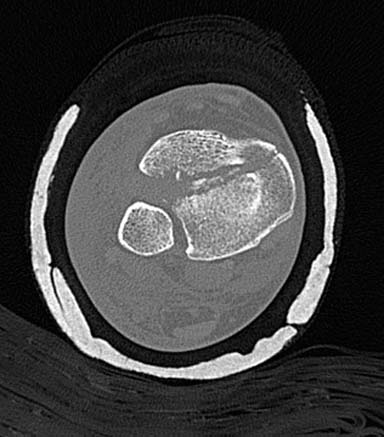

Первый случай, где перелом в результате падения с  небольшой высоты, где

мортиз рентген снимок показал отстутствие укорочения наружной

лодыжки и КТ срезы подсказали направления атаки. После такой фиксации

нет надобности в гипсовой повязке, брейс и через две недели движения в

суставе без нагрузки.